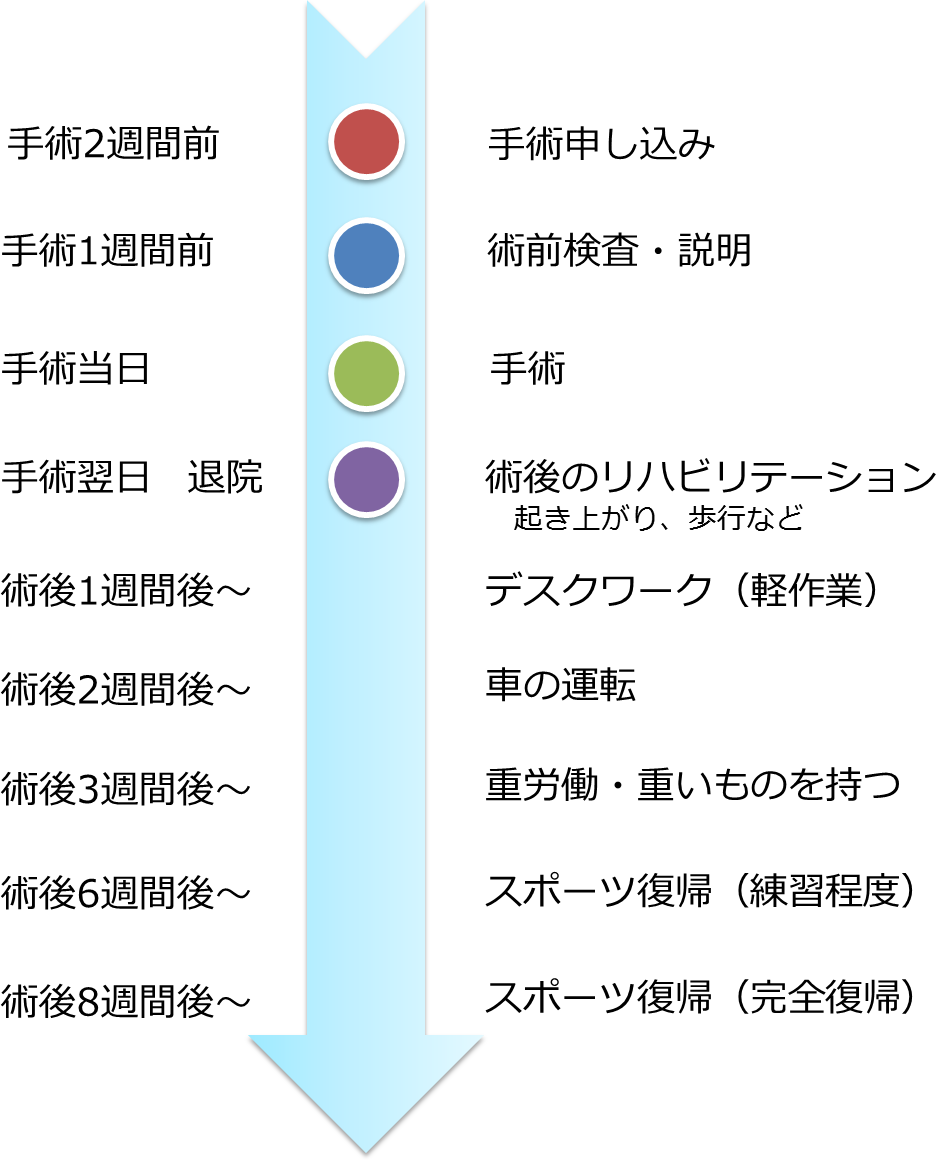

手術前から手術後までの流れは?

手術前から退院後までの流れは?